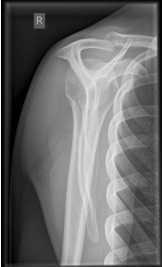

name the x-ray/position/method

transthoracic lateral shoulder (lawrence method)

evaluation criteria for transthoracic lateral shoulder (lawrence method)

Proximal ½ of humerus &

scapulohumeral joint

demonstrated without

superimposition of the

opposite shoulder

Overlying ribs & lung marking

blurred